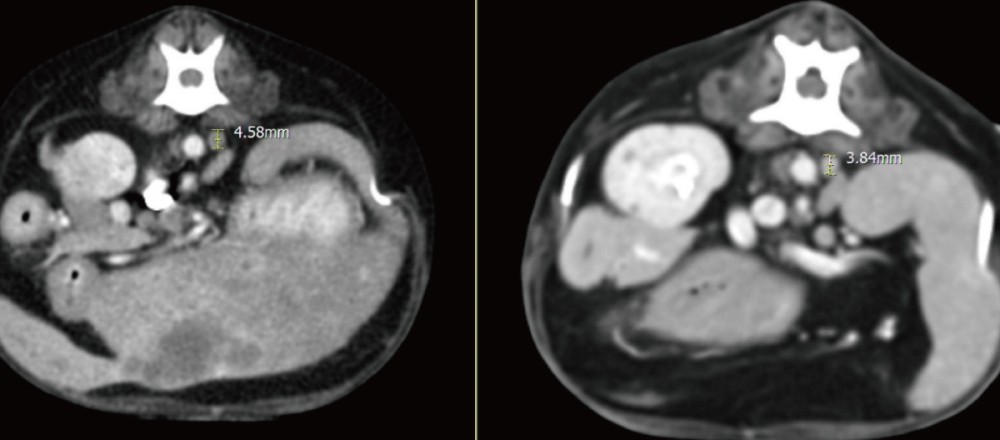

추가로 CT를 시행하였으며, 그 결과 간 실질 내 다발성 낭성 병변과 함께 췌장 석회화, 총담관 확장, 담석이 확인되었습니다.

실제로 추적 CT에서도 간 내 낭성 병변의 크기가 뚜렷하게 감소하고 림프절 크기 또한 감소하여 처치에 대한 반응이 명확하게 확인되었습니다 .

▲ 좌측 내측엽과 가측엽에 위치하던 cystic lesion의 크기 뚜렷한 감소 및 불규칙한 변연으로 변화

▲ 이전 검사에서 뚜렷하게 종대되어 관찰되었던 간 림프절 크기 감소